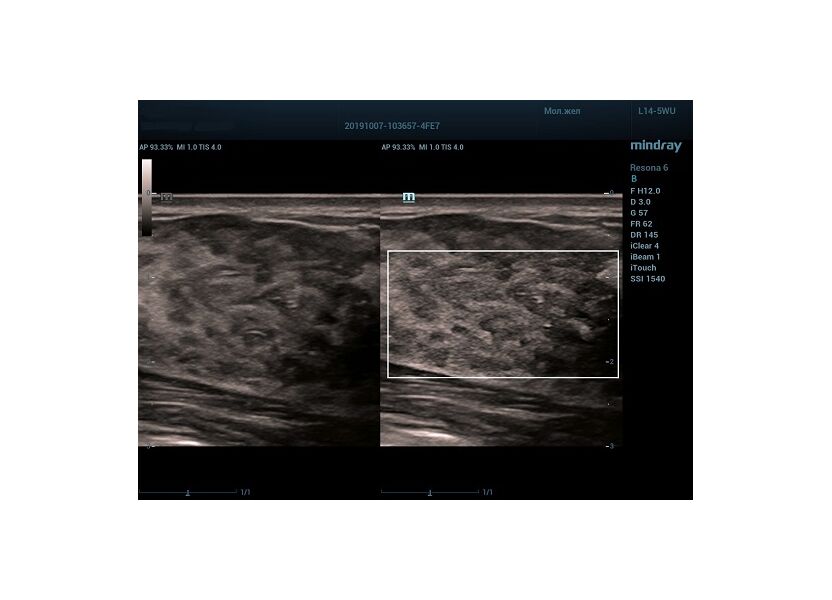

HD Scope позволяет достигать поразительной разрешающей способности выбранной зоны сканирования, при этом улучшая как детализацию, так и контрастность изображения. Помимо пространственного разрешения мы получаем преимущество и по разрешению во времени. Прибор получает огромное количество нативных изображений практически одновременно, и при сборе итоговой картины не происходит смещения объекта под датчиком, а значит и нет размывания изображения. Все участки раздела фаз, каждый контур образования теперь видны, мы все ближе к идеальной картинке.

Как он работает? Особенностью платформы ZST+, на которой построены приборы Mindray Resona, является так называемое многолучевое сканирование. В отличие от обычного датчика, который получает изображение в виде прямого эхо, датчики приборов этой серии проводят многолучевое сканирование каждым элементом с огромной скоростью, получая огромное количество данных. Затем происходит сложная постобработка и сбор из множества «многолучевых» снимков идеальной картинки.

Вторая особенность ультразвуковых машин данной линейки — это изменение расчетных констант распространения ультразвука, таким образом прибор перебирает для каждой ткани свои значения скоростей волны и пересчитывает каждую точку, делая менее выраженным поглощение по глубине. Эти особенности позволили использовать без фокусные технологии сканирования. Функция HD Scope позволяет использовать эти ресурсы для исследование небольшой области, значительно увеличивая качество изображения.